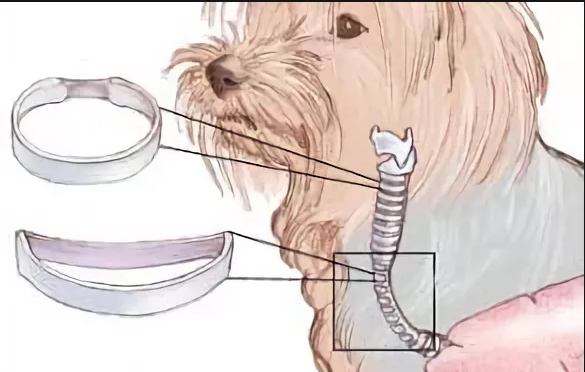

На сегодняшний день лучшие результаты получены при стентировании внутреннего просвета трахеи сеточными конструкциями, которые поддерживают просвет трахеи и способны выдерживать нагрузки, характерные для данной анатомической области.

В нашей клинике мы применяем нитиноловые стенты американской фирмы DEXTRONIX. ЭТО СПЕЦИАЛЬНО РАЗРАБОТАННЫЕ КОНСТРУКЦИИ ДЛЯ ИСПОЛЬЗОВАНИЯ У СОБАК И КОШЕК, изготовленные из сплава никеля и титана. Эти металлы не раздражают биологические ткани, одновременно являясь прочными и гибкими. Таким образом, они способны выдерживать большие нагрузки и при этом не вызывают воспалительных реакций со стороны организма. Оригинальное плетение изготовлено так, что составляющие сетку нити плетутся концами внутрь стента в направлении к центру, поэтому конец конструкции не раздражает и не травмирует прилегающую трахею.

Схематическое изображение степени колапса трахеи

DEXTRONIX- нитиноловые эндотрахеальные стенты